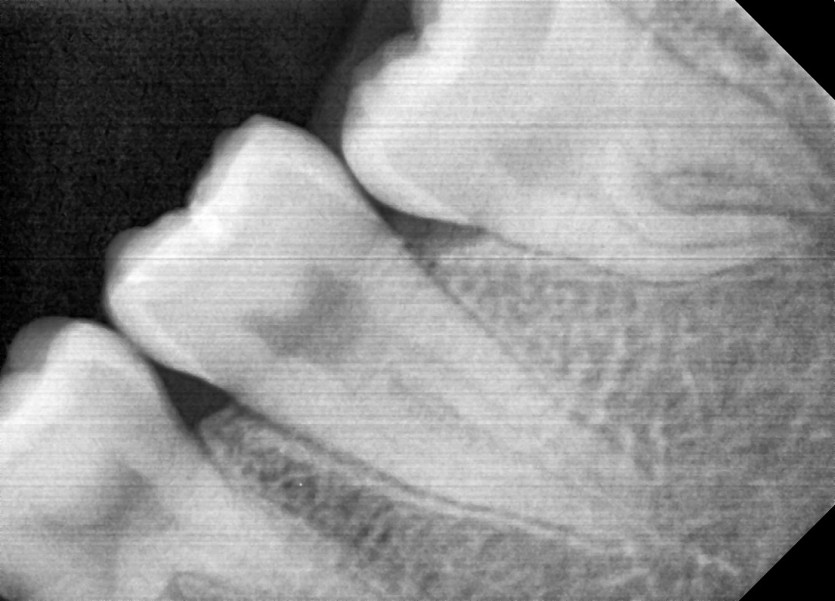

#28,38 사랑니 발치

구강외과 전문의가 당일 발치했습니다.